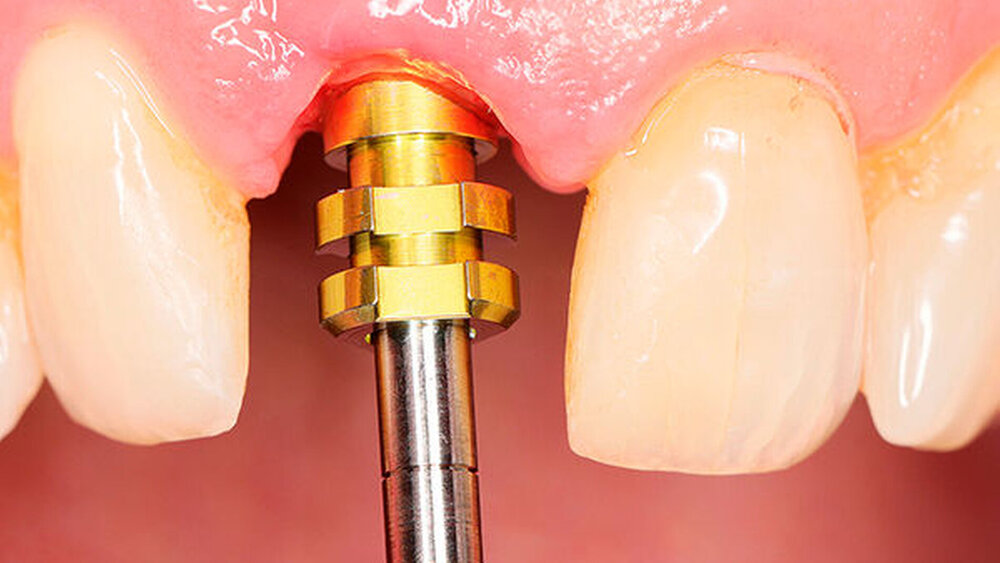

In welchen klinischen Anwendungen bietet das Implantat Vorteile?Hermann:Das neue CAMLOG PROGRESSIVE-LINE Implantat besticht durch sein innovatives parallel-konisches Makrodesign mit einem speziellen Gewinde, bei gleichzeitig bewährter Prothetikschnittstelle der Camlog-Linie. Dies bedeutet, dass in der chirurgischen Phase mit diesem Implantat eine zuverlässige Primärstabilität erzielt werden kann, speziell bei schwierigen anatomischen Voraussetzungen, wie z. B. bei der Sofortimplantation, bei reduzierter Kieferkammbreite oder konkav verlaufenden Alveoloarkämmen sowie bei weichem Knochen im Oberkiefer. Aufgrund des krestalen Verankerungsgewindes sehen wir zudem einen Vorteil bei der Platzierung des Implantats im Zusammenhang mit einer simultanen, offenen Sinusbodenelevation bei stark reduzierter Restknochenhöhe (2–3 mm). Auch einzeitige Verfahren lassen sich einfacher durchführen. Denn auch im kompromittierten Knochen erreicht das Implantat eine hohe vorhersagbare Primärstabilität.

Wie genau managen Sie die prothetische Versorgung?Hermann:Der Anwender kann auf die gewohnte CAMLOG oder CONELOG Prothetik zurückgreifen. Die Entscheidung für die konische oder flache (Butt-Joint) Schnittstelle bietet dem Anwender die Möglichkeit, mit ein und demselben Implantatkörper das Implantat entweder epikrestal oder leicht suprakrestal zu positionieren. Diese Wahlfreiheit kann bei Versorgungen etwa in ästhetisch anspruchsvollen Regionen eine Rolle spielen. Aufgrund der konischen Innenverbindung und des integrierten Platform Switch eignet sich das CONELOG PROGRESSIVE-LINE für eine subkrestale Positionierung.